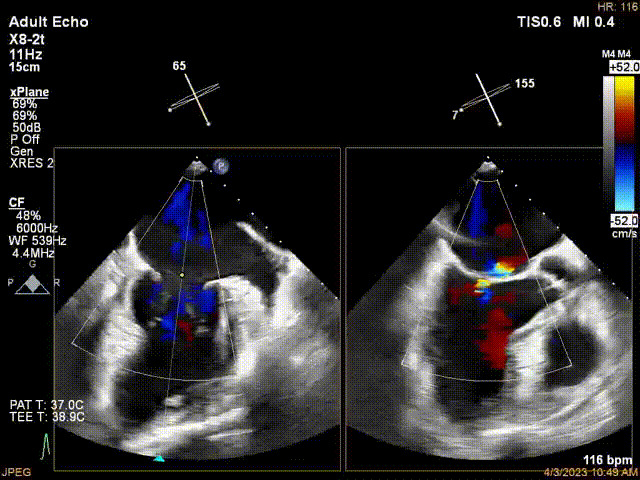

接受治療的是一例器質(zhì)性重度二尖瓣反流(DMR)患者,主訴“反復(fù)活動后胸悶,氣促3年余”。術(shù)前超聲顯示,雙房增大,二尖瓣脫垂伴重度反流,輕度三尖瓣反流,輕度肺高壓,升主動脈增寬。手術(shù)經(jīng)股靜脈-房間隔入路,采用全身麻醉插管,在TEE和DSA引導(dǎo)下完成房間隔穿刺。置入JensClip瓣膜夾系統(tǒng)后,在左房調(diào)整瓣膜夾的位置和軸向,后進入左室,在TEE引導(dǎo)下捕捉二尖瓣前后瓣葉,并關(guān)閉瓣膜夾。經(jīng)TEE反復(fù)確認手術(shù)效果后最終鎖定并釋放瓣膜夾。術(shù)后即刻超聲顯示瓣膜夾位置穩(wěn)定,功能良好,術(shù)前二尖瓣反流4+,術(shù)后0反流,肺靜脈逆流和左房壓都顯著好轉(zhuǎn),手術(shù)圓滿成功(以上數(shù)據(jù)都來源于醫(yī)院的臨床記錄)。術(shù)后患者狀態(tài)良好,目前已安排出院。

術(shù)后超聲顯示二尖瓣反流消失,瓣膜夾穩(wěn)定